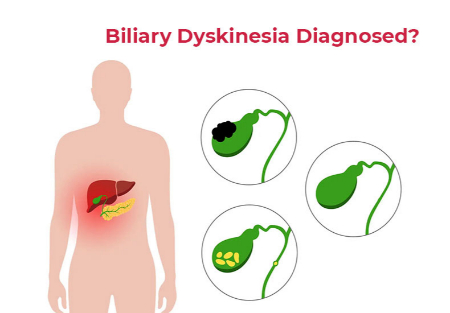

راههای تشخیص دیسکینزی صفراوی

از آنجایی که درد شکمی میتواند به دلیل سایر بیماریهای گوارشی مانند انسداد مجرای صفراوی، بیماری التهابی روده یا زخم معده رخ دهد، پزشکان از مجموعهای از معیارهای تشخیصی خاص برای تعیین اینکه آیا علائم شما ناشی از دیسکینزی صفراوی است یا خیر، استفاده میکنند. معیارهای تشخیصی شامل موارد زیر است:

• عدم وجود سنگهای صفراوی یا سایر رسوبات که ممکن است جریان صفرا را مسدود کرده باشند.

در صورت عدم درمان، دیسکینزی صفراوی میتواند منجر به عوارضی شود که به طور منفی بر سلامت شما تأثیر میگذارند، از جمله:

• کولهسیستیت: التهاب کیسه صفرا که ممکن است به دلیل عدم جریان صفرا در کیسه صفرا رخ دهد.

• سنگ صفراوی: تخلیه نامناسب کیسه صفرا که منجر به تشکیل سنگ صفرا میشود.